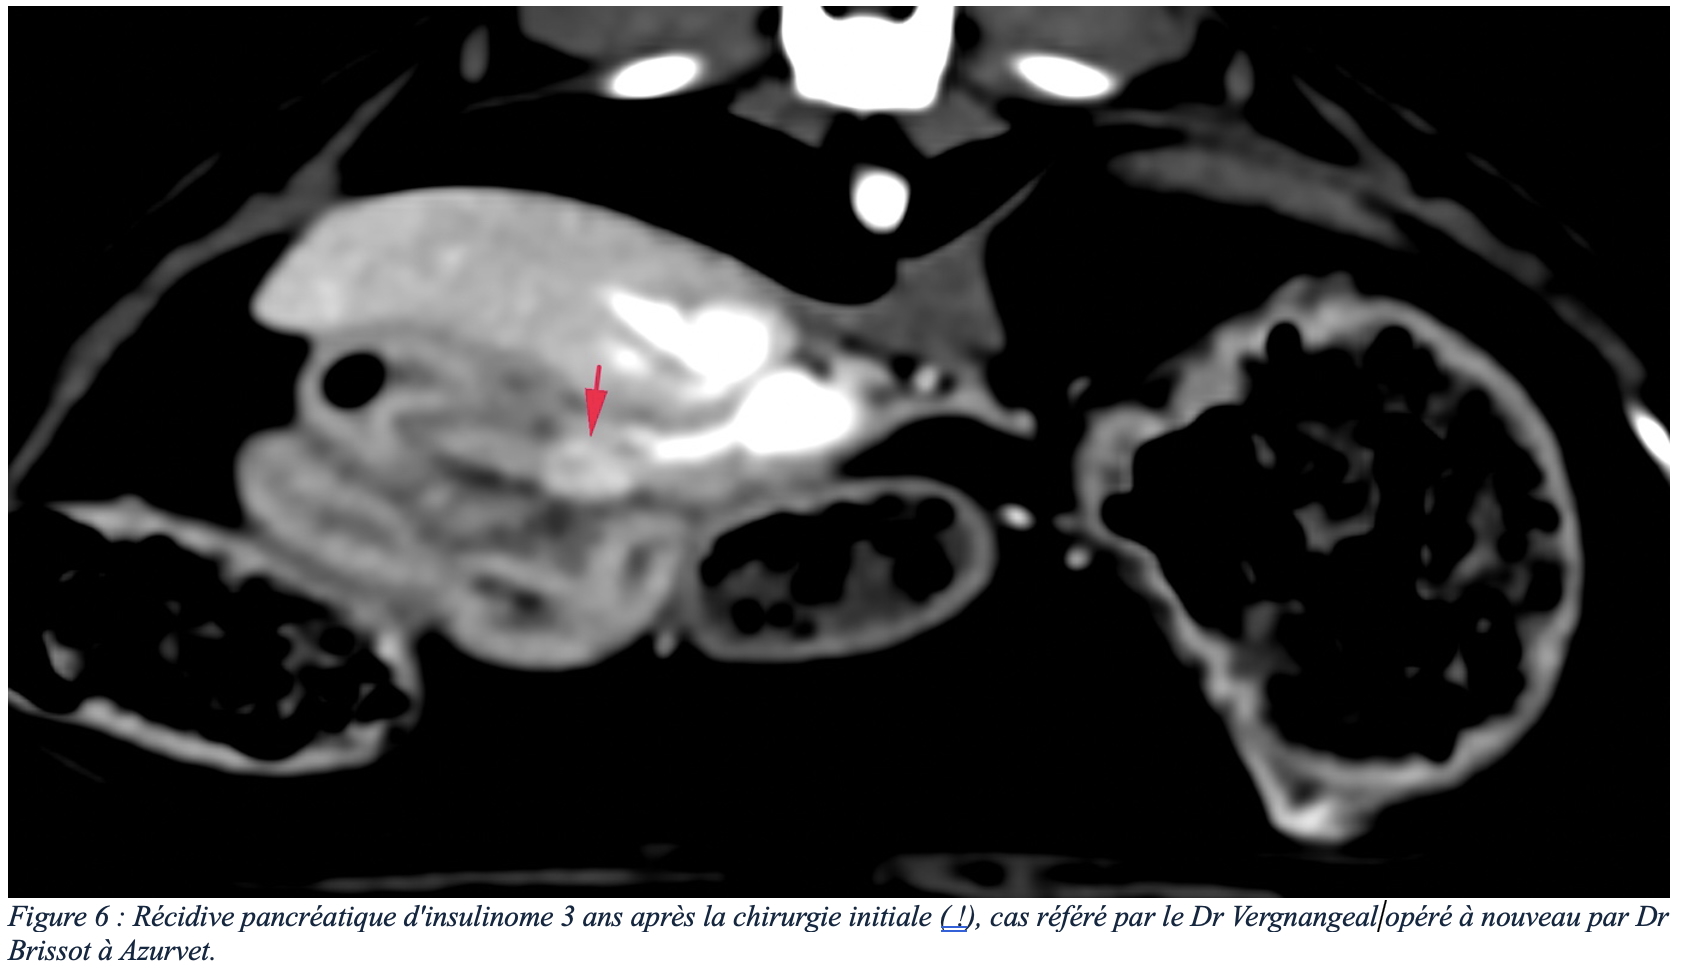

De l’expérience à Azurvet, certains animaux ont connu une première prise en charge chirurgicale couronnée de succès avec retour à une activité normale de l’animal. Certains de ces animaux ont même connu une récurrence des symptômes plusieurs mois après la chirurgie initiale, les examens d’imagerie ont ensuite mis en évidence un développement de récidive locale (figure 6) ou développement de métastases ganglionnaires et/ou hépatiques résécables (figure 7) permettant une seconde intervention, augmentant considérablement l’espérance de vie avec un confort satisfaisant.